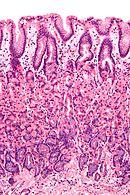

Isthmus of gland | Foveolar cells | Mucus gel layer | Fundic, cardiac, pyloric | Clear | ![]() |

Body of gland | Parietal (oxyntic) cells | Gastric acid and intrinsic factor | Fundic only | Acidophilic | ![]() |

Base of gland | Chief (zymogenic) cells | Pepsinogen and gastric lipase | Fundic only | Basophilic | ![]() |